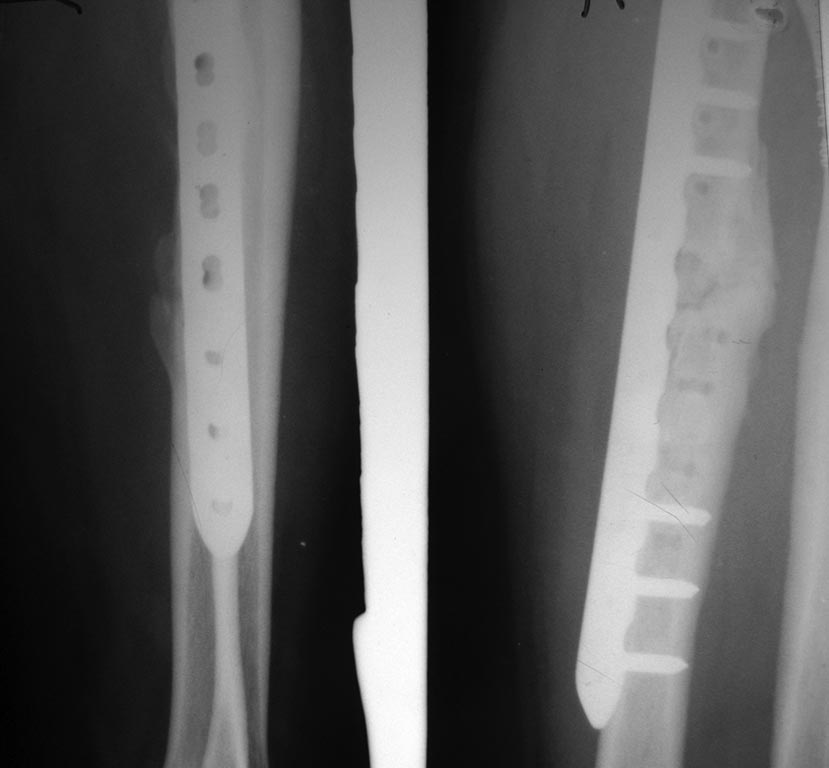

пластина.стержень.doc

94KB (96768 bytes)

Примерно так.ppt

83KB (84992 bytes)